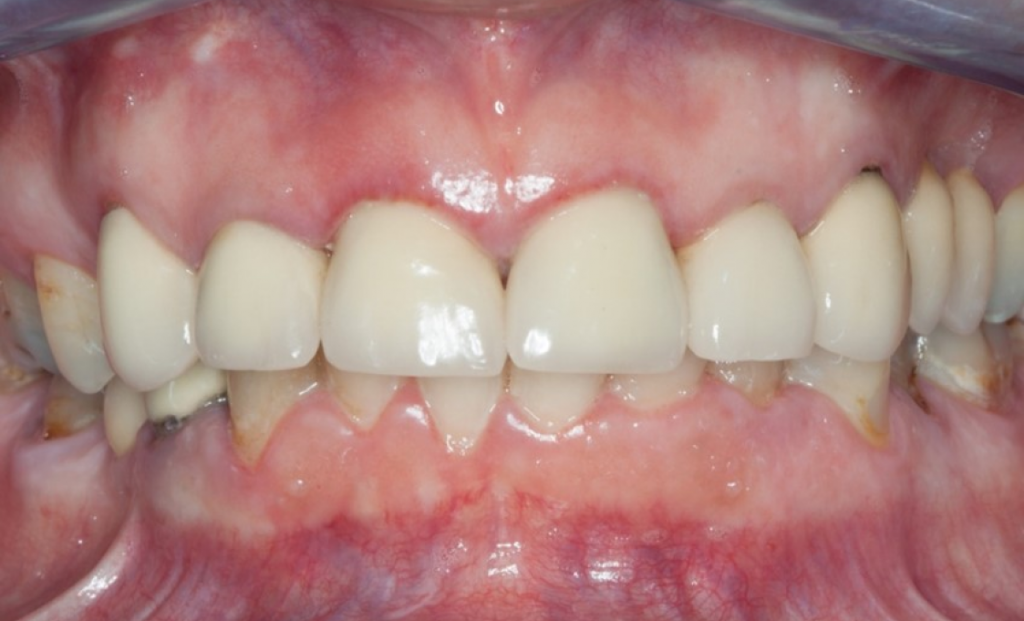

Рис. 23 Итоговый результат лечения с установленным мостовидным протезом 12-22 на имплантатах. Обратите внимание на естественный профиль ткани после извлечения 12, 11, 21 и 21